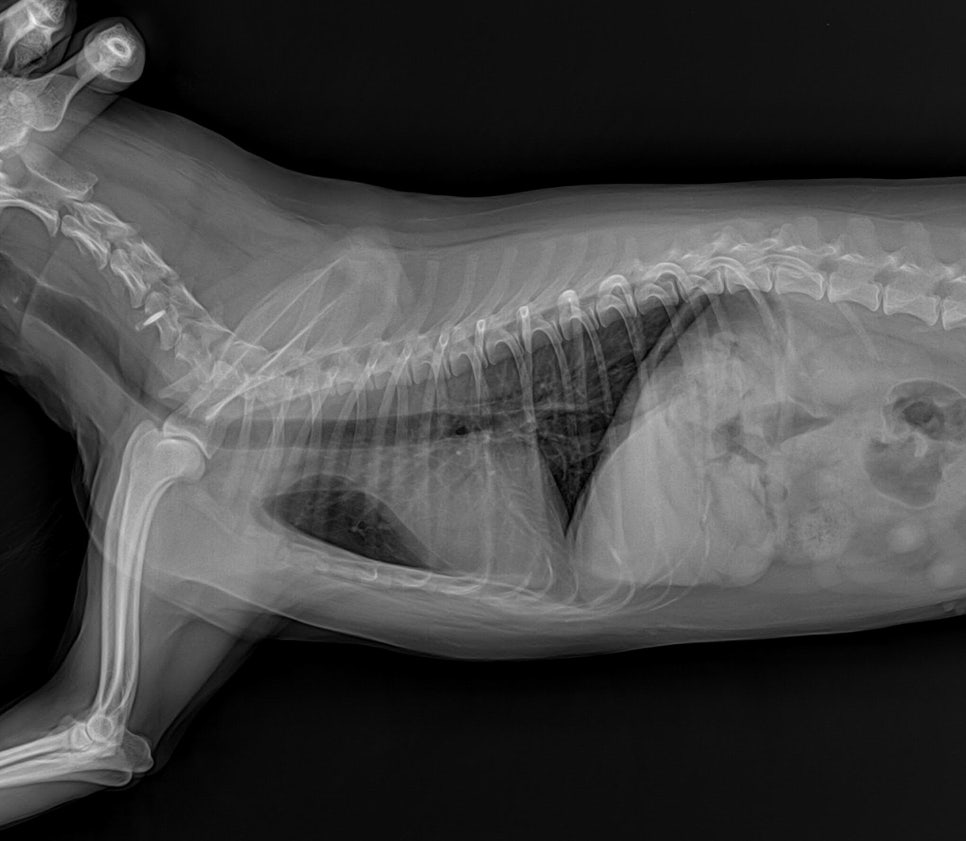

환자 복부 방사선 사진/ 출처: 라온동물메디컬센터